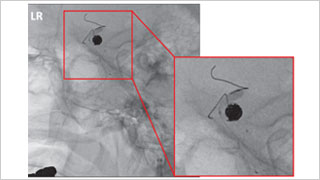

日本医科大学 脑神经外科,博慈会纪念综合医院 脑神经外科

佐藤 俊